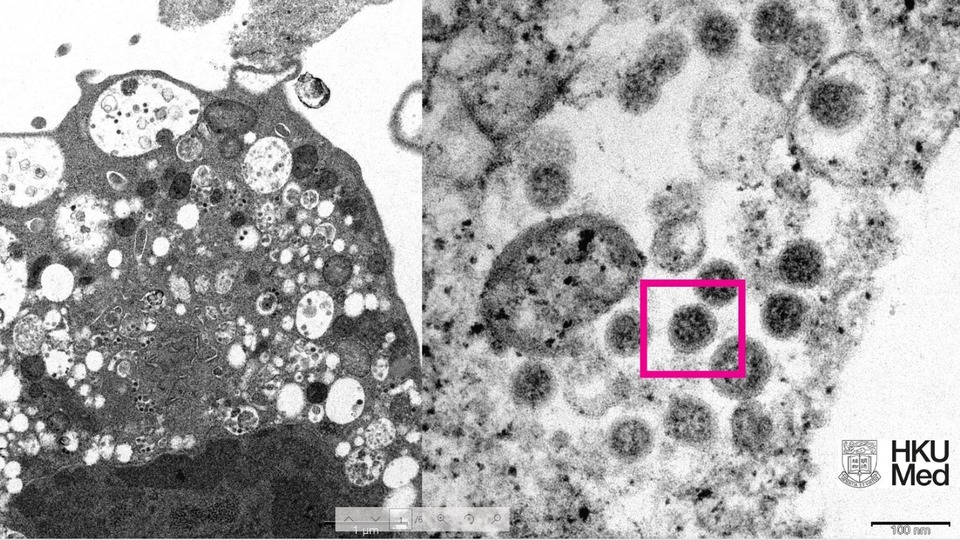

Hong Kong Üniversitesi Li Ka Shing Tıp Fakültesi'nden yapılan açıklamada, araştırmacılar tarafından SARS-CoV-2 virüsünün Omicron varyantının elektron mikroskobu görüntüsünün ortaya çıkarıldığı belirtildi.

Üniversite tarafından yayınlanan fotoğrafın solunda, küçük siyah viral partiküller içeren şişmiş veziküllerle hücre hasarını gösteren, SARS-CoV-2 Omicron varyantı ile enfeksiyondan sonra bir maymun böbrek hücresinin (Vero E6) düşük büyütmeli elektron mikrografının yer aldığı ifade edildi.

Fotoğrafın sağında ise yüzeylerinde korona şekilli sivri uçlara sahip viral partikül kümelerini gösteren enfekte bir Vero E6 hücresinin yüksek büyütmeli elektron mikrografının yer aldığı belirtildi.